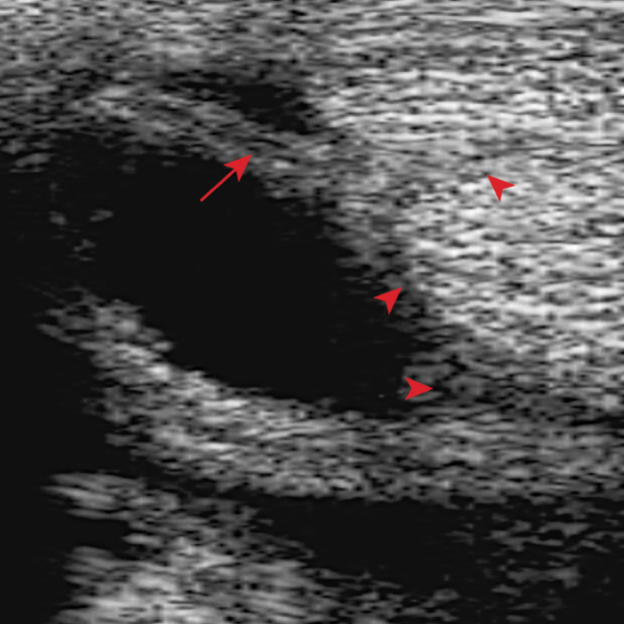

- The sheath is distended by anechoeic fluid. Arrow showing the swollen vincula and the arrowheads show swollen synovium surrounding the tendons.